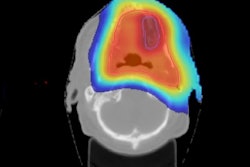

The main goal of radiotherapy is to maximize the damage to the tumor while minimizing the damage to the surrounding healthy tissue, thereby reducing acute and late side effects. The most frequently used radiotherapy modalities use high-energy (MeV) photon or electron beams. Conventional x-ray radiation therapy is characterized by almost exponential attenuation and absorption, delivering the maximum energy near the beam entrance, but continuing to deposit significant energy at distances beyond the cancer target.

The maximum energy deposition for x-ray beams with energy of about 8 MeV is reached at a depth of 2 cm to 3 cm in soft tissue. To deliver dose optimally to the tumor, while protecting surrounding healthy tissues, radiotherapy has progressed rapidly with the development of new technologies and methodologies. The latest developments include MRI-guided radiotherapy, which combines simultaneous use of MRI and photon irradiation. Such advanced radiation therapy modalities are becoming increasingly important and offer new opportunities to treat different cancers, in particular the combination with other emerging areas such as cancer-immunotherapy and the integration of sequencing data, with clinical decision-support systems for personalized medicine.

Figure 1: For protons and other ions the peak of energy loss occurs just before the particles reach a halt. This is called the Bragg peak, first put to use at Lawrence Berkeley Laboratory to treat the first patient with protons in 1954.However, if one looks at the dose deposition profile of photons compared with other particles (figure 1), the conspicuous feature of this graph is that, in the case of protons and carbon ions, a significant fraction of the energy is deposited in a narrow depth range near the endpoint of the trajectory, after which very little energy is deposited. It was precisely these differences in dose -- the so-called Bragg-peak effect -- that led visionary physicist and founder of Fermilab, Robert Wilson, to propose the use of hadrons for cancer treatment in 1946.